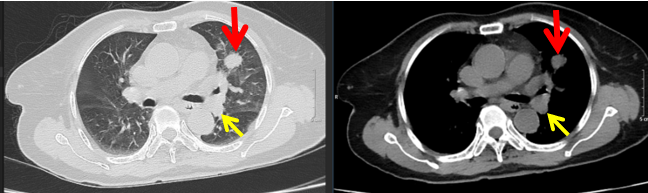

- Chụp cắt lớp vi tính ngực: Hình ảnh u thùy trên phổi trái kích thước 36x28mm, bờ không đều, ngấm thuốc mạnh sau tiêm, rốn phổi trái có vài hạch kích thước lớn nhất 17x19mm, bờ không đều, ngấm thuốc không đều sau tiêm.

Hình 1:  Hình ảnh chụp cắt lớp vi tính ngực: U thùy trên phổi trái kích thước 36x28mm (mũi tên màu đỏ), hạch rốn phổi trái (mũi tên màu vàng).